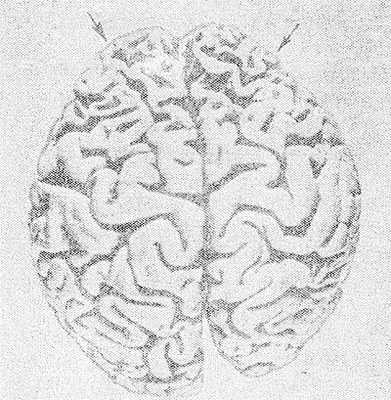

Рис. 1. Макропрепарат головного мозга при болезни Пика: выраженная атрофия извилин коры лобных долей (указано стрелками) и уменьшение размеров правого полушария головного мозга.

Патологоанатомические изменения при П. б. характеризуются избирательной атрофией гл. обр. коры и белого вещества полушарий головного мозга. Иногда атрофия в значительно меньшей степени захватывает подкорковые узлы и стволовые отделы. Различают атрофию преимущественно лобных (рис. 1) или височных долей, нередко — комбинированное их поражение. Часто в процесс вовлекаются теменные доли, однако изолированное их поражение, так же как и атрофия затылочных долей, встречается крайне редко. При атрофии лобных долей прецентральные извилины обычно остаются сохранными. Атрофия развивается, как правило, в симметричных участках обоих полушарий, иногда с большей выраженностью в левом и крайне редко — в правом полушарии.